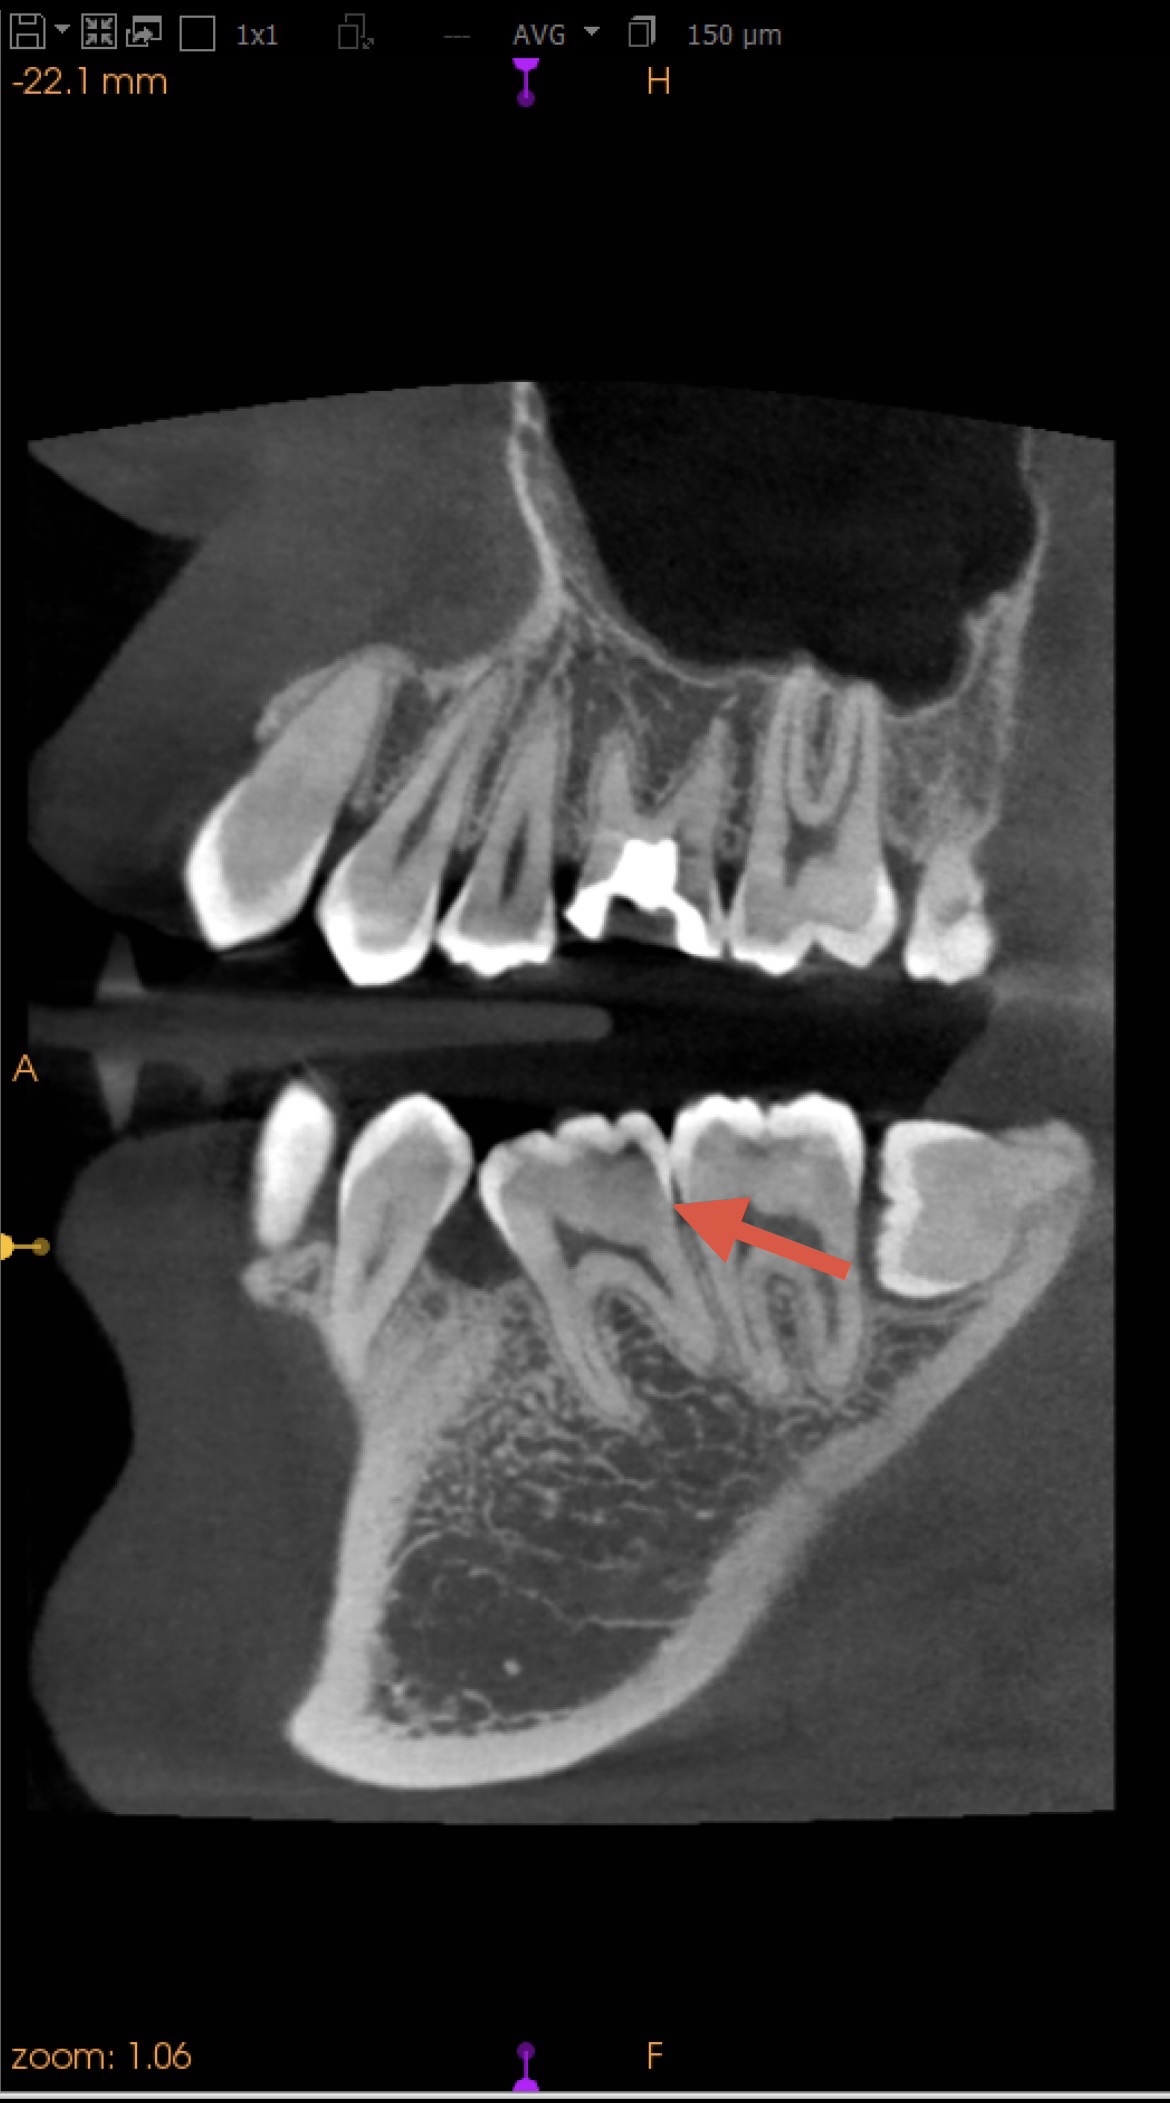

【治療前】左下第一大臼歯

MTA詰める前→詰めた後